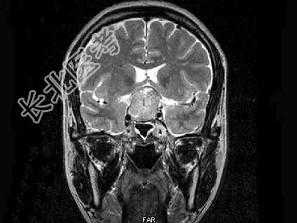

- 单项选择题男,49岁, 1年前发现双颞侧视野缺损,视物模糊, 查体:双颞侧偏盲, 根据所提供图像,最可能的诊断为 ( )

A、垂体微腺瘤

B、颅咽管瘤

C、脑膜瘤

D、嫌色细胞腺瘤

E、生殖细胞瘤